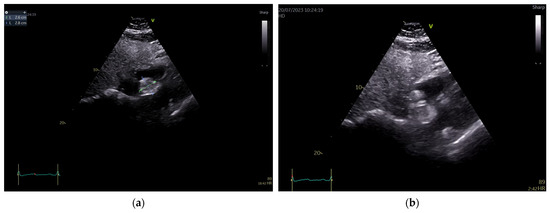

To better describe it, a transesophageal echocardiography was performed. We were surprised to see a second similar so-called mass at the superior pole of the IAS, with the same aspect as described with transthoracic echo. In fact, the IAS was intensely thickened in a diffuse manner except for the fossa ovalis and had the appearance of an “hourglass”, suggesting a possible lipomatous hypertrophy of the interatrial septum. Using both bidimensional (Figure 2) and tridimensional echo (Figure 3), the masses seemed to be encapsulated, homogenous, and attached to the IAS while clearly not being a part of it, aspects that raised some questions in this special patient. There was no color Doppler signal inside the masses, suggesting a lack of vascularization. They lacked any contact and/or continuity with the cardiac valves, an aspect that helped in the differential diagnosis with certain tumors originating on these structures. The right atrial walls were not clearly and entirely viewed. Also, the fact that these masses were not described during previous evaluations was quite unusual. The appearance did not resemble that of a thrombus, since even if the patient had thrombophilia, she was well anticoagulated, and the position and shape of the “masses” did not resemble thrombi. A malignant tumor/metastasis should have been more invasive, irregular, and not respecting the fossa ovalis. The echocardiographic structure of the masses could have resembled a cardiac myxoma though, but possessing two such masses respecting the FO was uncommon. The same situation applies to other possible benign tumors and/or endocarditis. A possible abscess in the context of endocarditis should have also yielded high-inflammation markers. Cardiac amyloidosis was excluded since it did not spare the FO and there were also no other signs of this pathology. Papillary fibroelastoma is usually attached to heart valves, and hemangioma can be found anywhere, most frequently in the LV and RV but also in the RA. Rhabdomyomas are usually found in the ventricular walls and valves, in infants and children. Fibroma is most frequently found in the ventricles, in infants, children, and young adults. Myxoma is normally diagnosed between 30 and 60 years of age, or even earlier if part of Carney syndrome. It can be located anywhere in the heart, but most often within the IAS, pediculated and protruding in the LA. However, a myxoma is a gelatinous non-homogenous mass, due to areas of necrosis and/or hemorrhage, and it sometimes has a villous surface, characteristics that helped exclude this pathology. There are usually multiple malignant tumors which can also be found in any part of the heart. They are irregular masses with an extensive/invasive nature. The most frequent is angiosarcoma which is often located in the RA. Metastatic tumors reach the heart either by direct extension, lymphatic and hematogenous extension, or intracavitary extension through the vena cava and/or pulmonary veins. They are most often secondary disseminations from lung cancer (men) and/or breast cancer (women) [3,7,8,14].

Figure 2.

Bidimensional transesophageal echocardiography, modified bicaval view. Two so-called sessile masses (24–27 mm), at the level of the IAS respecting the fossa ovalis, with the appearance of separate structures.

Figure 3.

Transesophageal echocardiography, tridimensional reconstruction. (a) Four-dimensional zoom acquisition revealing two so-called masses attached to the IAS with the appearance of distinct structures, bulging in the RA (inferior) and imprinting the LA surface of the IAS (superior); (b) 4D zoom acquisition after multislice analysis, confirming the homogenous aspect of the “structures”.